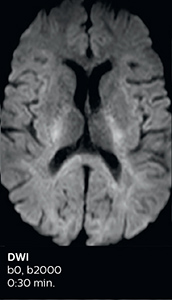

Improved diffusion imaging in stroke patients

Using MultiBand SENSE allowed the staff to improve their diffusion quality. “Our diffusion sequence was already fast before, about 40 seconds. Now with Elition, it still lasts 40 seconds, but we improved the spatial resolution by 0.2 mm and use high b-values to be more sensitive to visualize changes related to acute stroke,” says Dr. Savatovsky.

Fast acute stroke protocol

This is an example of acute ischemic stroke with distal occlusion of the right posterior cerebral artery. Note the improved visibility of the ischemic territory on the diffusion weighted image with high b-value. The 3D FLAIR shows a distal PCA occlusion. The fast SWIp depicts the thrombus on the isolated second echo image. The total scan time (including SmartBrain, preparations and a fast 3D T1w TSE Gd) is 8:00 minutes.